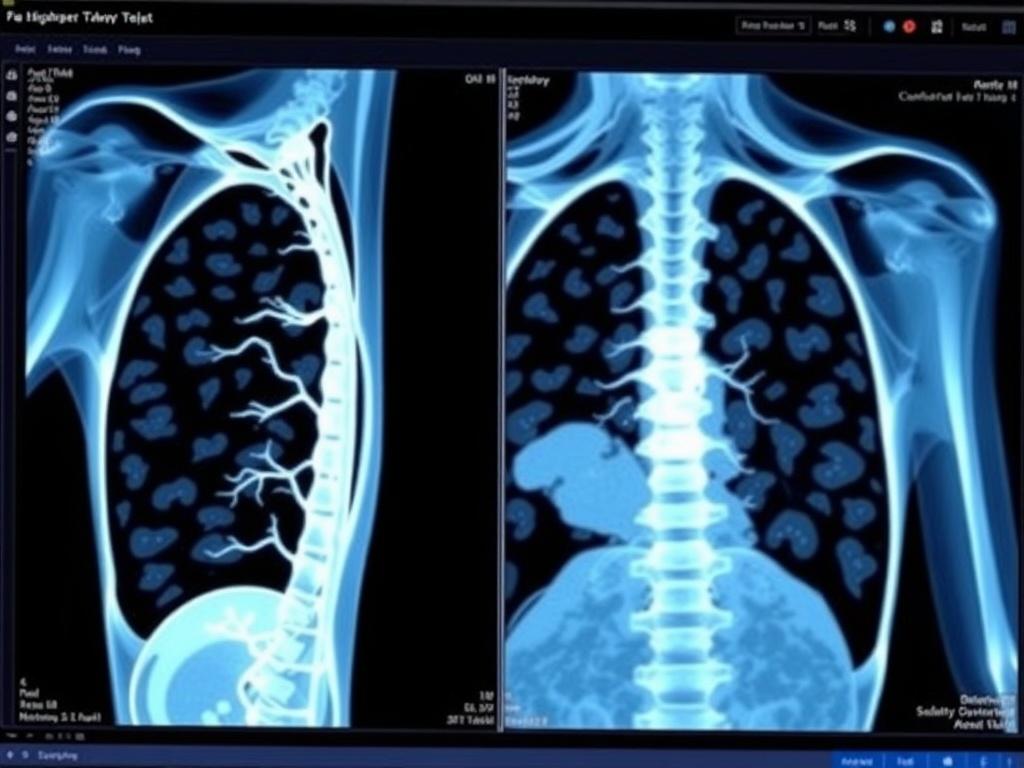

DICOM — это стандарт для хранения и передачи медицинских изображений и связанных с ними данных. Он описывает, как упаковать снимок и метаданные, чтобы разные устройства и программы могли их прочитать. На практике DICOM-файлы бывают большими и содержат десятки срезов, поэтому нужен удобный инструмент для просмотра.

Онлайн-вьюер — это веб-приложение, которое открывает DICOM прямо в браузере. Вы не устанавливаете толстые клиенты, не переносите флешки с дисками, а просто открываете ссылку. Это удобно для удалённых консультаций, обучения и ситуаций, когда нужно делиться изображениями быстро и без лишней подготовки.